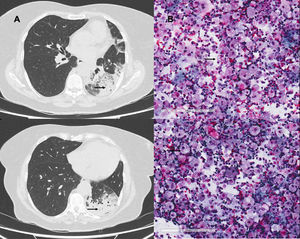

A 69-year-old woman, former smoker who stopped 20 years previously, with no other background of interest, had a 30-year history of using of Vaseline lip balm up to 6 times a day. She presented in the respiratory medicine clinic with a 2-month history of non-productive cough, dyspnea on minimal exertion, and temperature of 37 °C in the last few days. Examination showed an oxygen saturation of 93% in room air and bilateral crackles. Chest X-ray revealed bilateral multiple consolidations. Chest computed tomography located these multifocal consolidations in the left hemitorax and basal segments of the right lower lobe consistent with pneumonic changes.1 Treatment began with dual antibiotic therapy, with little clinical and radiological improvement. Bronchoscopy was performed with bronchoalveolar lavage that was negative for microbiological culture, fungi and mycobacteria, while bronchial cytology findings showed abundant macrophages with foamy vacuolated cytoplasm consistent with lipoid pneumonia associated with the excessive use of petroleum jelly. Discontinuation of this product resulted in clinical and radiological improvement in subsequent follow-ups (Fig. 1).

Exogenous lipoid pneumonia is an uncommon disease caused by lipid deposition within the pulmonary alveoli, which may be caused by absorption of oily agents such as Vaseline lip balm.2